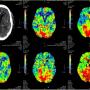

Defying All Odds: Successful Thrombolysis in a Nonagenarian with Posterior Circulation Infarct